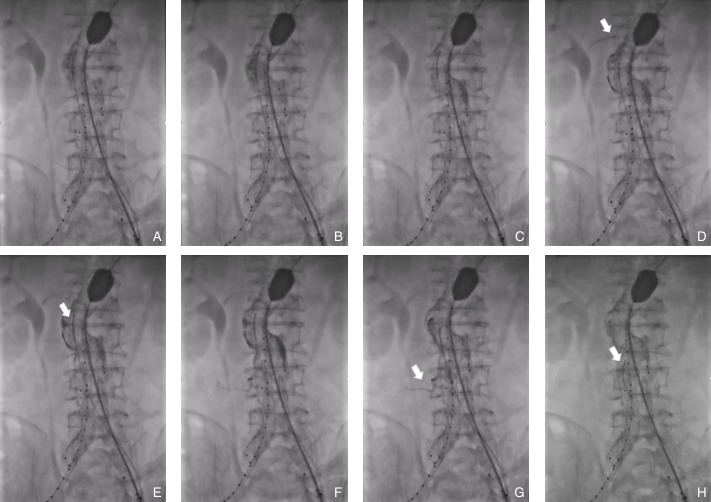

图4 注入纤维蛋白粘合剂过程 A:预置导管注入造影剂示踪;B:注入纤维蛋白粘合剂;C:纤维蛋白粘合剂在瘤腔内弥散;D:副肾动脉显影;E:调整导管位置;F:继续注入纤维蛋白粘合剂;G:腰动脉显影;H:调整导管位置角度,继续注射,腰动脉未显影Fig.4 Process of fibrin sealant injection A: Contrast injection through the pre-positioned catheter for tracking; B: Injection of fibrin sealant; C: Dispersion of fibrin sealant within the aneurysm sac; D: Visualization of an accessory renal artery; E: Adjustment of catheter position; F: Continued injection of fibrin sealant; G: Visualization of a lumbar artery; H: Adjustment of catheter angulation followed by continued injection, with no further visualization of the lumbar artery